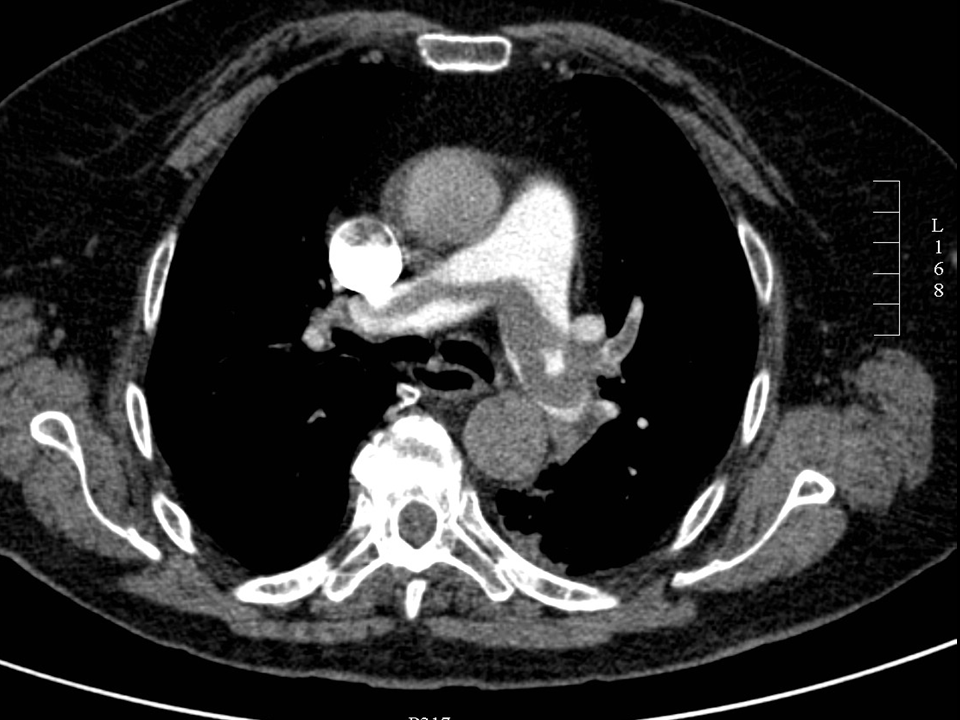

• Aortic rupture occurs after rapid deceleration it is usually located at the transition of the aortic arch and the descending aorta, as the aortic arch more mobile than the descending aorta, it can be diagnosed with CT angiography.

• Pulmonary embolisation should be investigated with pulmonary CT angiography examination. Conventional chest radiography is negative in the majority of the acute cases. Indirect signs, such as pleural effusion, ipsilateral elevated diaphragm, atelectases or infarct pneumonia only appear after a longer period of time. As opposed to this, CTA provides a swift and precise diagnosis.

15. Elderly female with dyspnea. ECG shows abnormalities suggestive of pulmonary embolisation. CTA with bolus-tracking technique reveals a „saddle embolus” causing massive filling defect within the pulmonary trunk.

• Aorta aneurysm rupture – aorta dissection

If the patient is stable, immediate CT angiography is the diagnostic choice. In case of suspected dissection CTA should be performed with ECG gating.